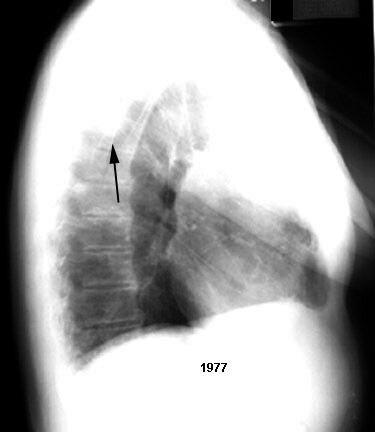

Gradual progression Central calcium Probable tuberculoma

Gradual progression

Central calcium

Probable tuberculoma